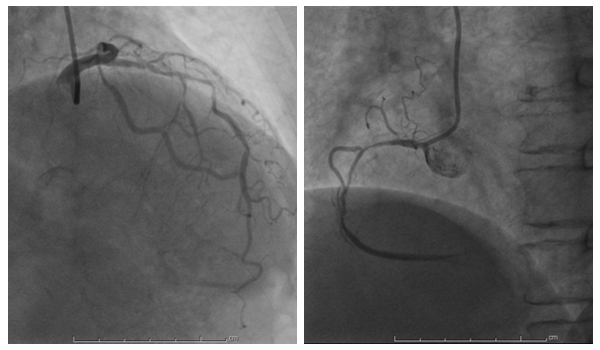

董爷爷术前冠脉血管病变

65岁董爷爷,2年前突发呼吸困难,当时外院诊断“支气管哮喘”,经治疗后好转。但仍反复出现活动后气喘、咽痛;没精神,喜睡,有气无力,平素勾着背走路,眼睛看事物模糊不清。发病来多家医院就诊,平时服药不规律、自行停用、或者服用偏方等,病情不断加重。近1年出现下肢重度浮肿,结合症状、心电图及胸部CT,我科考虑“冠心病可能性大”。进一步完善冠脉造影示:心脏冠脉3条大血管严重狭窄,其中前降支弥漫性狭窄50%-90%,右冠状动脉慢性完全闭塞。手术难度大,建议进一步心脏支架植入术或者胸外科行冠脉搭桥手术。

董爷爷术后前降支血管通畅